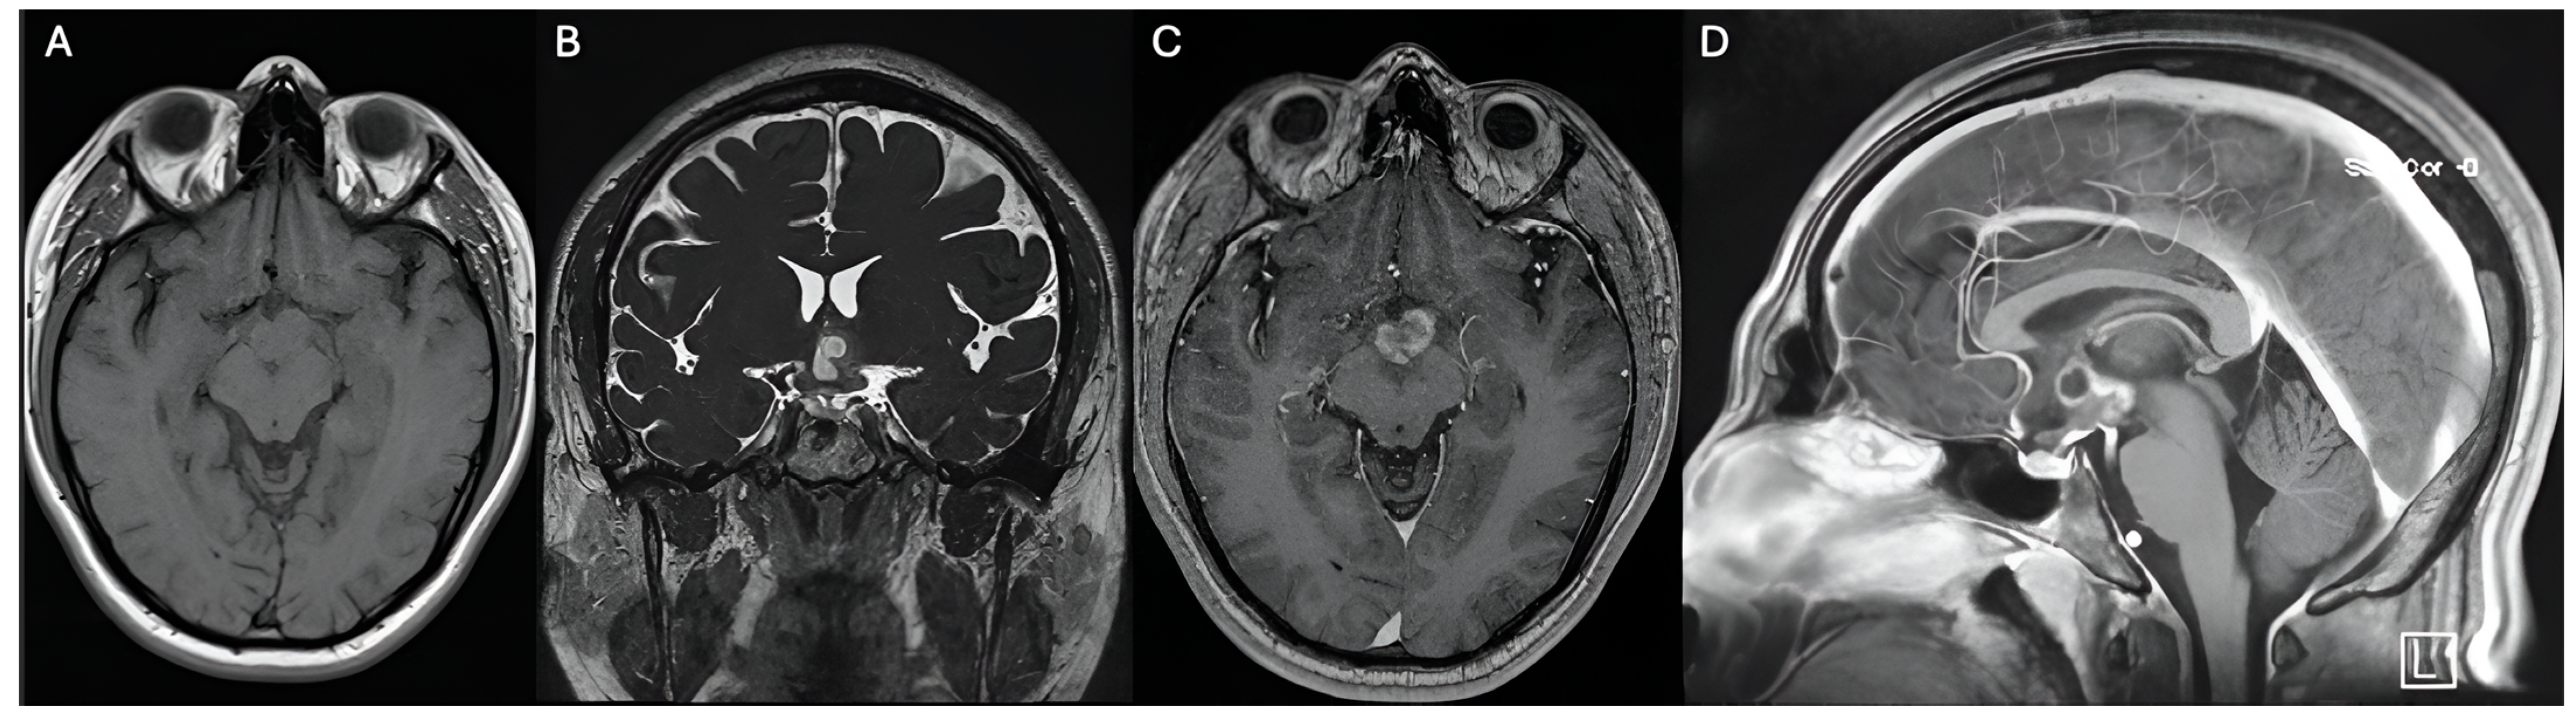

Figure 1. Preoperative MRI shows a hypothalamic lesion that is isointense on T1 (A), hyperintense on T2 (B), partially enhances contrast (C), and has a small cystic component superiorly (D). No evidence of calcifications. The hypothalamic lesion has an approximate volume of 8.03 cm3.

The MRI was subsequently conducted using a navigation protocol, which revealed a well-circumscribed lesion in the hypothalamic region that was clinically and anatomically consistent with a low-grade astrocytoma. The optic chiasm, pituitary stalk, and adjacent neurovascular structures were all in close proximity to the tumor, which presented substantial risks if conventional surgical intervention were pursued.

Hypothalamic gliomas differentiate from optic gliomas such that they are seen as large masses in the suprasellar region infiltrating the brain parenchyma and third ventricle, while optic gliomas infiltrate along the optic pathway [11]. Hypothalamic gliomas typically present as rounded or lobulated solid masses located above the Sella turcica [12]. Hypothalamic gliomas appear hypointense on T1-weighted sequences and hyperintense on T2-weighted [12,13] and FLAIR sequences, with larger tumors being heterogeneous and containing both cystic and solid components. The solid component exhibits significant contrast enhancement [13]. The enhancement pattern can change over time without any clinical significance. If the tumor extends upwards and compresses the third ventricle and the foramen of Monro, hydrocephalus might result. Infiltration of the subarachnoid spaces might occur, showing brightness on T2-weighted images and a ring of enhancement [12]. The presumptive diagnosis of our case was pilocytic astrocytoma due to the presence of a hypothalamic multilobulated lesion that enhanced with contrast with an associated cystic lesion. Hypothalamic hamartoma was ruled out since contrast enhancement was evident, likewise, the clinical manifestations of our case were different from gelastic seizures [14,15]. Craniopharyngioma diagnosis was not considered due to the absence of calcifications associated with the tumor and the cyst component was not hyperintense in T1 [16].